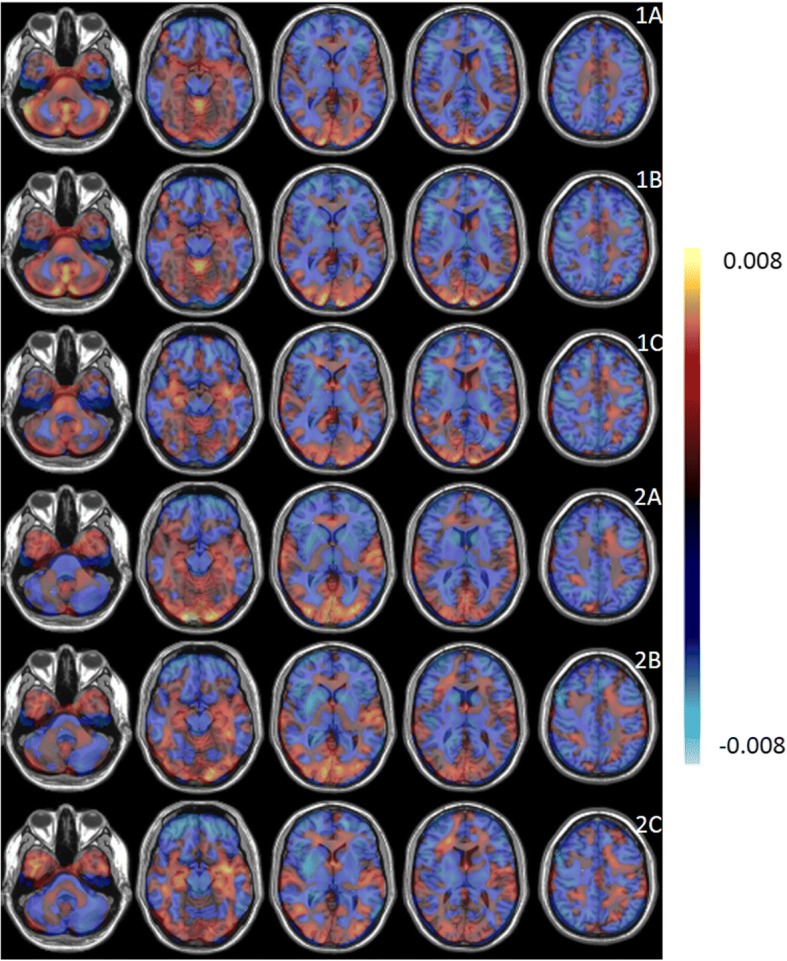

The performance measures for a classification between ALS versus HC and PP versus HC for SVM, PCA-SVM, and PCA-LR are given in Table 2. RV coefficients between the pairs of individual ALS- and PP-specific pattern expressions scores are given in Table 3 for the three classifiers. Since the RV coefficients demonstrated a high correlation between ALS- and PP-specific pattern expression scores for all three classifiers, only the individual ALS- and PP-specific pattern expression scores as determined by PCA-SVM were used to classify both groups using a linear SVM. The average ROC curve for this SVM classification, based on disease-specific pattern expression scores and evaluated by a tenfold CV, is illustrated in Fig. 2, with a corresponding AUC of 0.91 and a prediction accuracy of 85% (point along ROC curve with identical sensitivity and specificity). Individual ALS- and PP-specific pattern expression scores, averaged over the ten random iterations, as determined by PCA-SVM are plotted in Fig. 5, together with the hyperplane (in this case a line) separating both groups as determined by a linear SVM. ALS- and PP-specific metabolic brain patterns, obtained by differentiating ALS and PP patients from HC and including all image data for training, are illustrated in Fig. 4 for the three classifiers. Again positive values, marked in red, indicate regions of relative hypermetabolism in ALS or PP patients compared to HC, whereas the negative values, indicated in blue, correspond to relative, regional hypometabolism in ALS or PP patients compared to HC. Specifically for the ALS-specific brain pattern, relative hypometabolism in the frontal and parietal cortex and relative hypermetabolism in the anteromedial temporal cortex was observed while the PP-specific brain patterns demonstrated relative hypometabolism in the striatum, pons and frontal cortex, and cerebellum. The voxelwise Pearson correlation coefficients between the disease-specific patterns as determined by the three classifiers are given in Table 3, demonstrating a consistently high correlation (≥ 0.66) between disease-specific glucose metabolic brain patterns.

Second, we showed that different classifiers can be used to generate both disease-discriminative (Fig. 3) and disease-specific (Fig. 4) glucose metabolic brain patterns using 18F-FDG brain PET imaging. Since ALS patients match a positive and PP patients a negative pattern score, positive weights in the disease discriminative pattern constitute hypermetabolism in ALS patients compared to PP patients while negative pattern weights correspond to hypometabolic brain regions in ALS patients compared to PP patients. This same holds for the disease-specific ALS and PP pattern where an ALS or PP patient corresponds to a positive pattern score and thus positive pattern weights correspond to hypermetabolism in ALS and PP patients compared to healthy controls while negative weights represent hypometabolic brain regions in ALS and PP patients compared to healthy controls. Correlating the pairs of individual projection scores for a ALS- and PP-specific metabolic brain pattern determined by each of the three methods resulted in a RV coefficient of 0.93 on average (Table 3). Similarly, the voxelwise Pearson correlation coefficient for the disease-specific patterns demonstrated the strong correlation between ALS and PP patterns as determined by the three classifiers, with a lower correlation between patterns determined by SVM and PCA-LR (r value of 0.70 for ALS and 0.66 for PP respectively). The lower correlation between SVM and PCA-LR patterns could be explained by the fact that SVM and PCA handle noise and intersubject variability differently. Although, these patterns demonstrated visually the same main regions of hyper- and hypometabolism. Overall, the generated ALS- and PP-specific patterns were very similar to the ALS and PP patterns that have been discussed extensively in literature. Specifically, for ALS patients, relative hypometabolism in the frontal and parietal cortex and relative hypermetabolism in the anteromedial temporal cortex, in the absence of concomitant frontotemporal dementia, cerebellum, and brainstem have been observed [ref. 11]. In contrast, PP patients have relative hypometabolism in the striatum and according to the subtype, relative hypometabolism in the pons and frontal cortex (PSP), relative hypometabolism in the cerebellum (MSA), and a very asymmetric relative hypometabolic pattern in CBD [ref. 11, ref. 30–ref. 32]. As such, the generated PP pattern is a composition of different subtype patterns and therefore masks some subtype-specific characteristics such as the CBD-specific hypometabolic asymmetry. On the other hand, the highly accurate classification results implied that the generated patterns are to be considered as disease-specific for ALS and PP or discriminative between ALS and PP. Therefore, the glucose metabolic brain patterns reflect disease pathogenesis and hold information about diagnosis and prognosis. This way, this pattern not only supports differential diagnosis but can also have an added value for assisting visual reading.